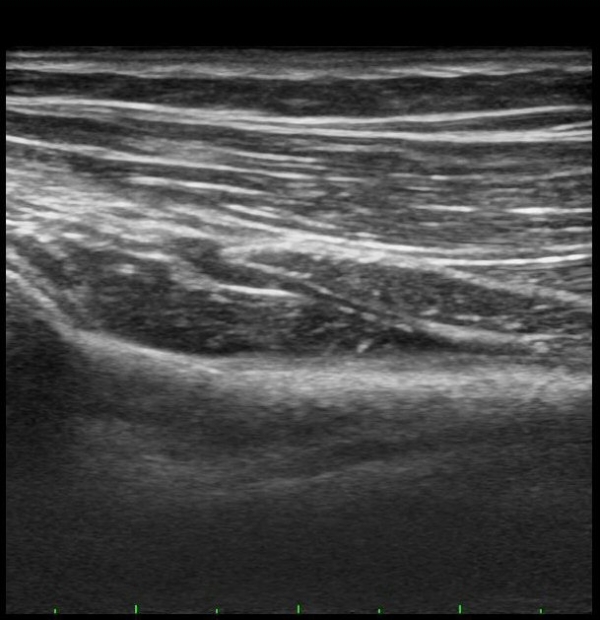

ŽÃËÀÚ¸¦ Á» ´õ ¸»´ÜÀ¸·Î À̵¿ÇÏ´Ï Èİñ°£½Å°æÀÌ È¸¿Ü±Ù ¸»´Ü¿¡¼­ Ç¥ÃþÀ¸·Î ³ª¿À´Â °ÍÀÌ °üÂûµÊ(±×¸² 3).